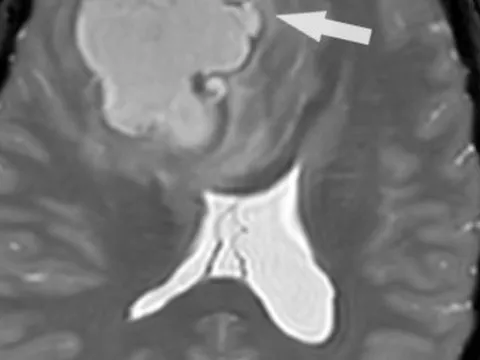

Khối u 5 cm trốn trong não nữ bệnh nhân Campuchia

Chị T.H, 30 tuổi, người Campuchia, bị đau đầu dữ dội kèm chóng mặt, buồn nôn, đi khám thì phát hiện một khối u 5 cm